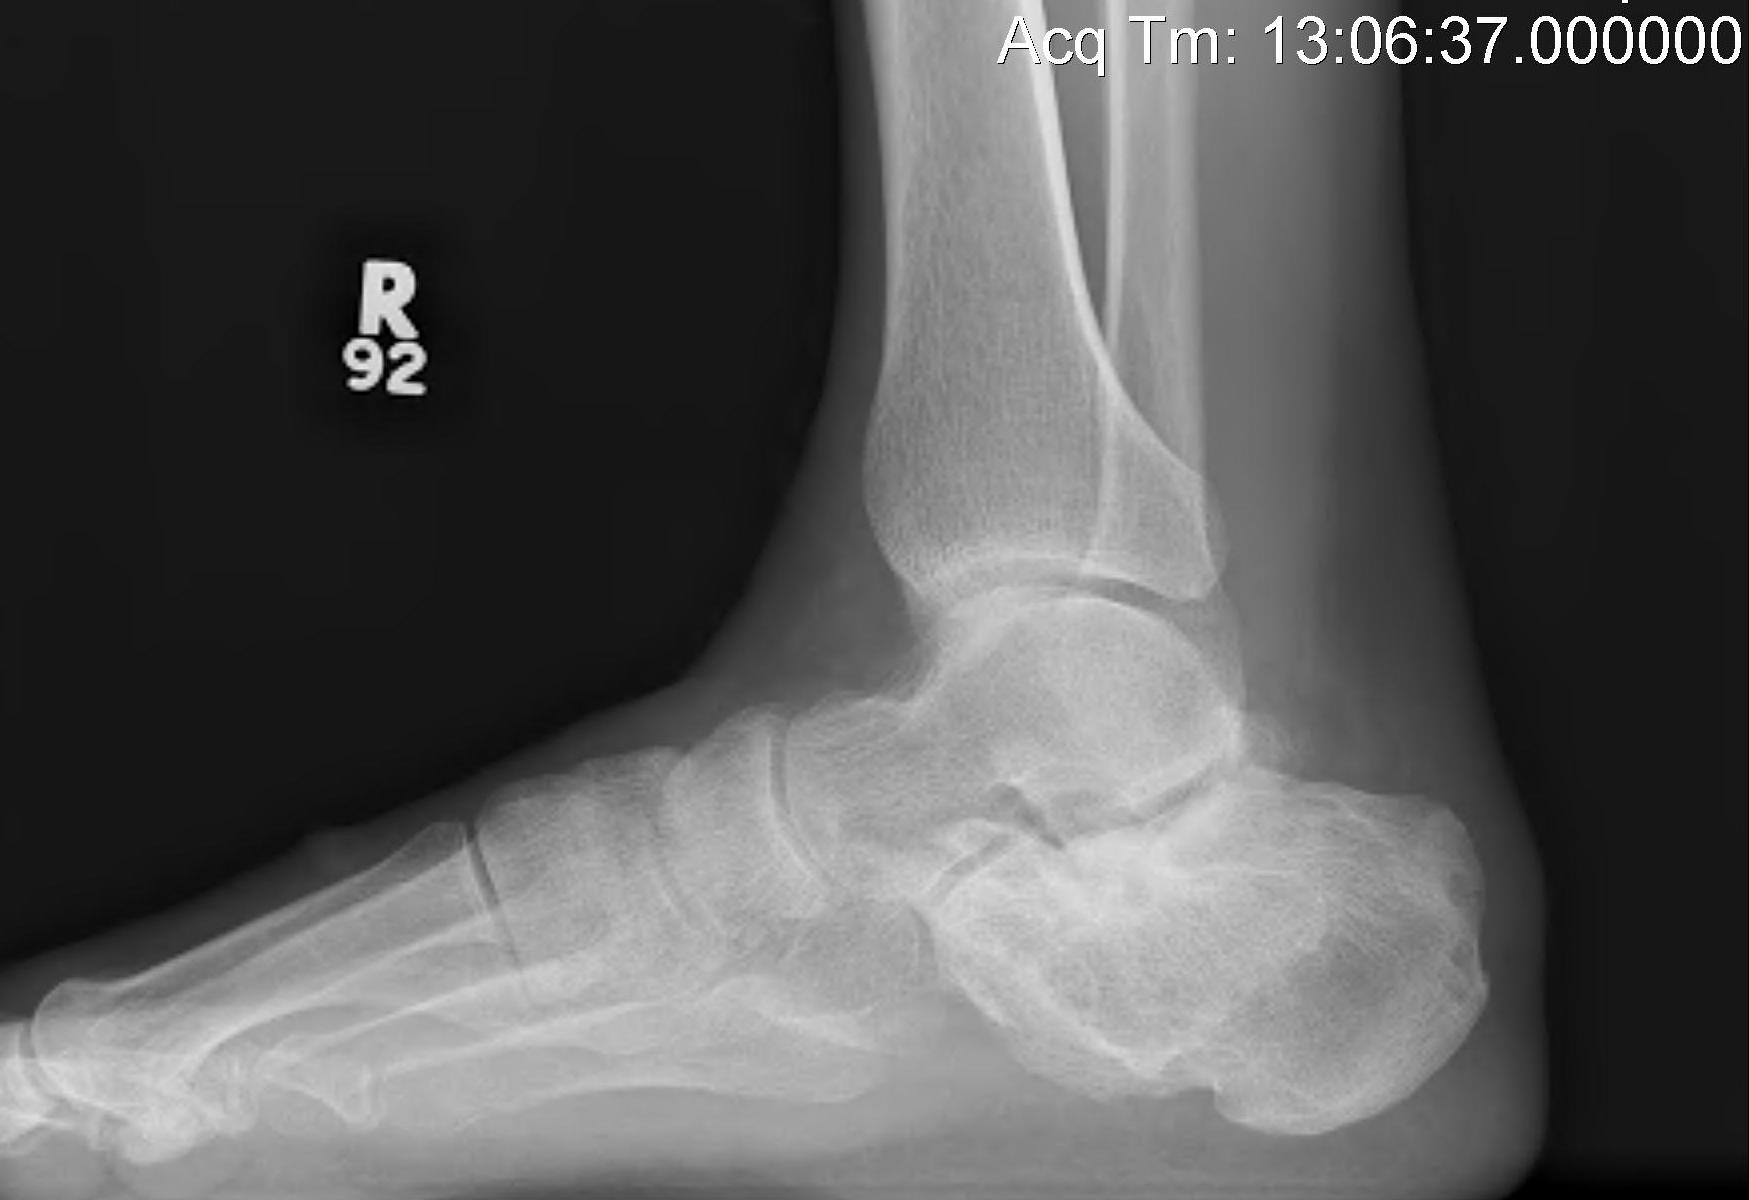

Indication

Isolated STJ arthritis with minimal deformity